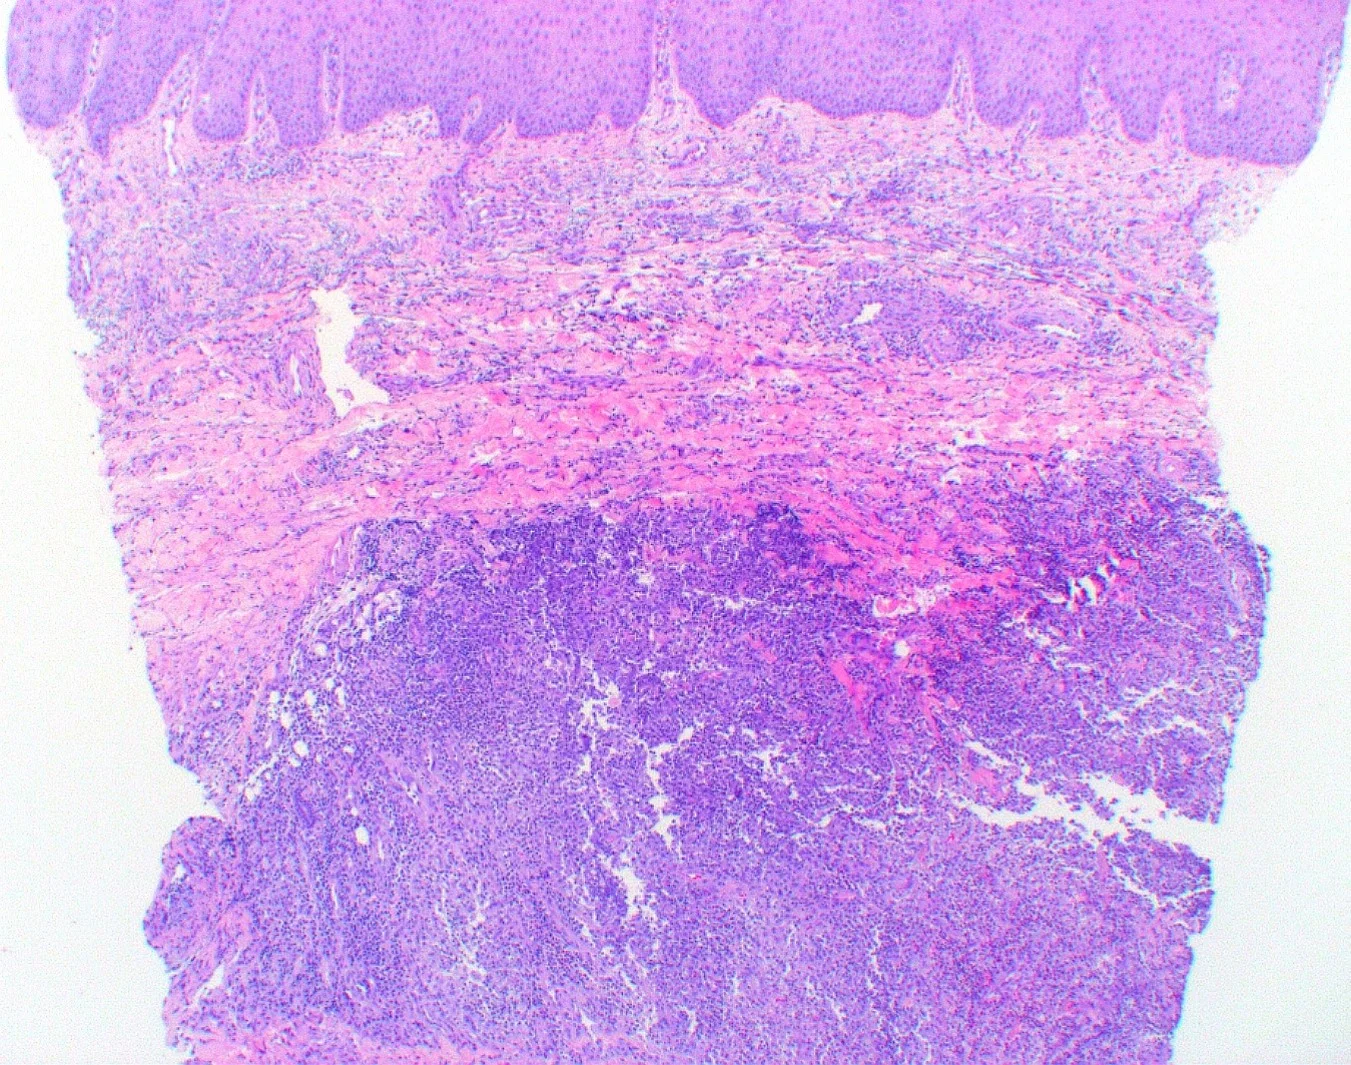

62 year old male. Acute swelling of right index finger. 6 months ago had triamcinolone injection into digital mucous cyst in same finger with good response. Failing response to bacterial antibiotics a biopsy was taken for histology and culture.